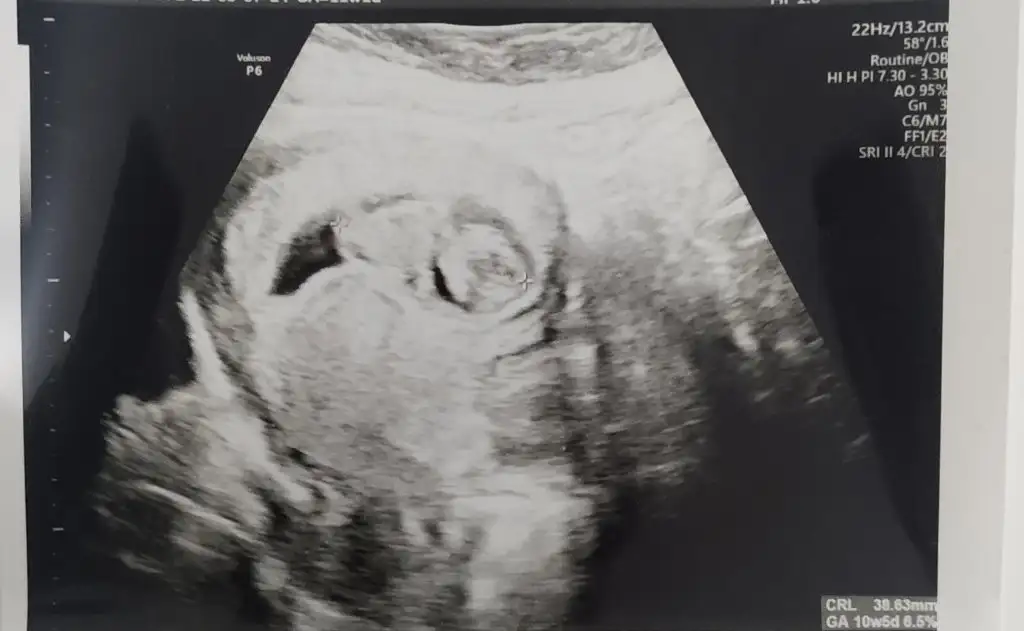

Yaa banada bakarmisiniz 10+3 vajinal bakıldı bugün 🙏🥰

Burada 8 haftalık karından canım